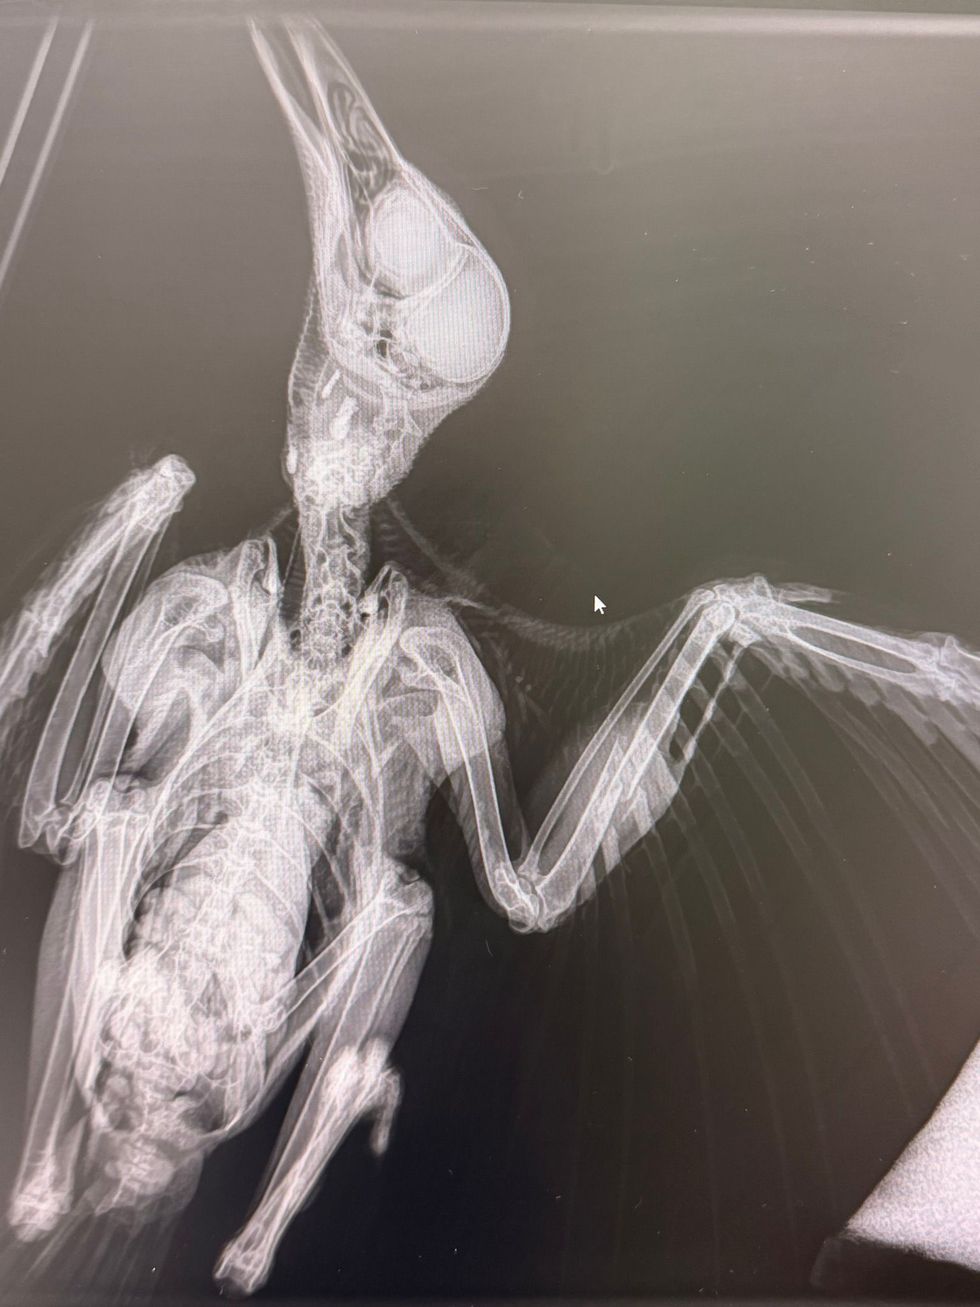

The injured crow being cared for in the home of Dr Justyn Loveridge (Vets for Pets/PA)

An X-ray showed it had fractured a bone and Dr Loveridge assessed that the wing could be repaired and the bird rehabilitated with a couple of weeks of care.